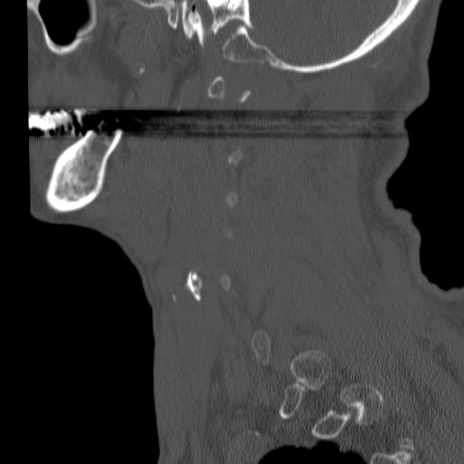

症例46 頚椎CT(矢状断像)

【症例】80歳代男性

【主訴】両側頚部〜上肢のしびれ

【現病歴】昨日、自宅内で転倒、その後より上記症状あり。意識障害なし。

【身体所見】両側上肢のallodynia(熱痛覚過敏)あり。MMTおよびDTRは正確な所見取れず。両上肢の挙上はなんとか可能。

異常所見と診断は?